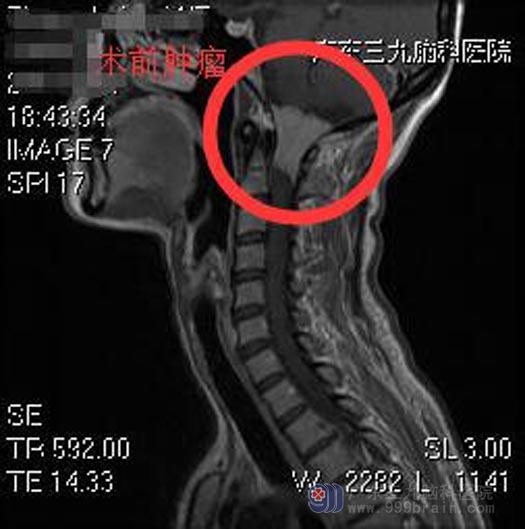

头颅CT检查发现:枕骨大孔区占位性病变,性质待查;广东三九脑科医院头颅MR检查提示:枕骨大孔区偏左侧-颈2水平椎管内占位性病变,范围约为3.8cm×2.7cm×2.2cm,病变紧贴邻近硬脊膜,并包埋邻近左侧椎动脉V4段,延髓及部分颈髓受压移位。

综合神经外科鲁明主任告诉他,肢体麻木症状就是这个病灶所引起,一经确诊,建议手术切除。王老师了解病情后,同意手术方案。鲁明主任主刀,在全麻下行枕骨大孔区偏左侧-颈2水平椎管内脊膜瘤切除术,术中见枕骨大孔区偏左侧-颈2水平椎管内灰柏色肿瘤组织,质软,包膜完整,分块予以全切除,术中对神经保护良好。术后,王老师的四肢麻木感明显好转。病理回报:血管瘤型脑膜瘤,WHO I级。